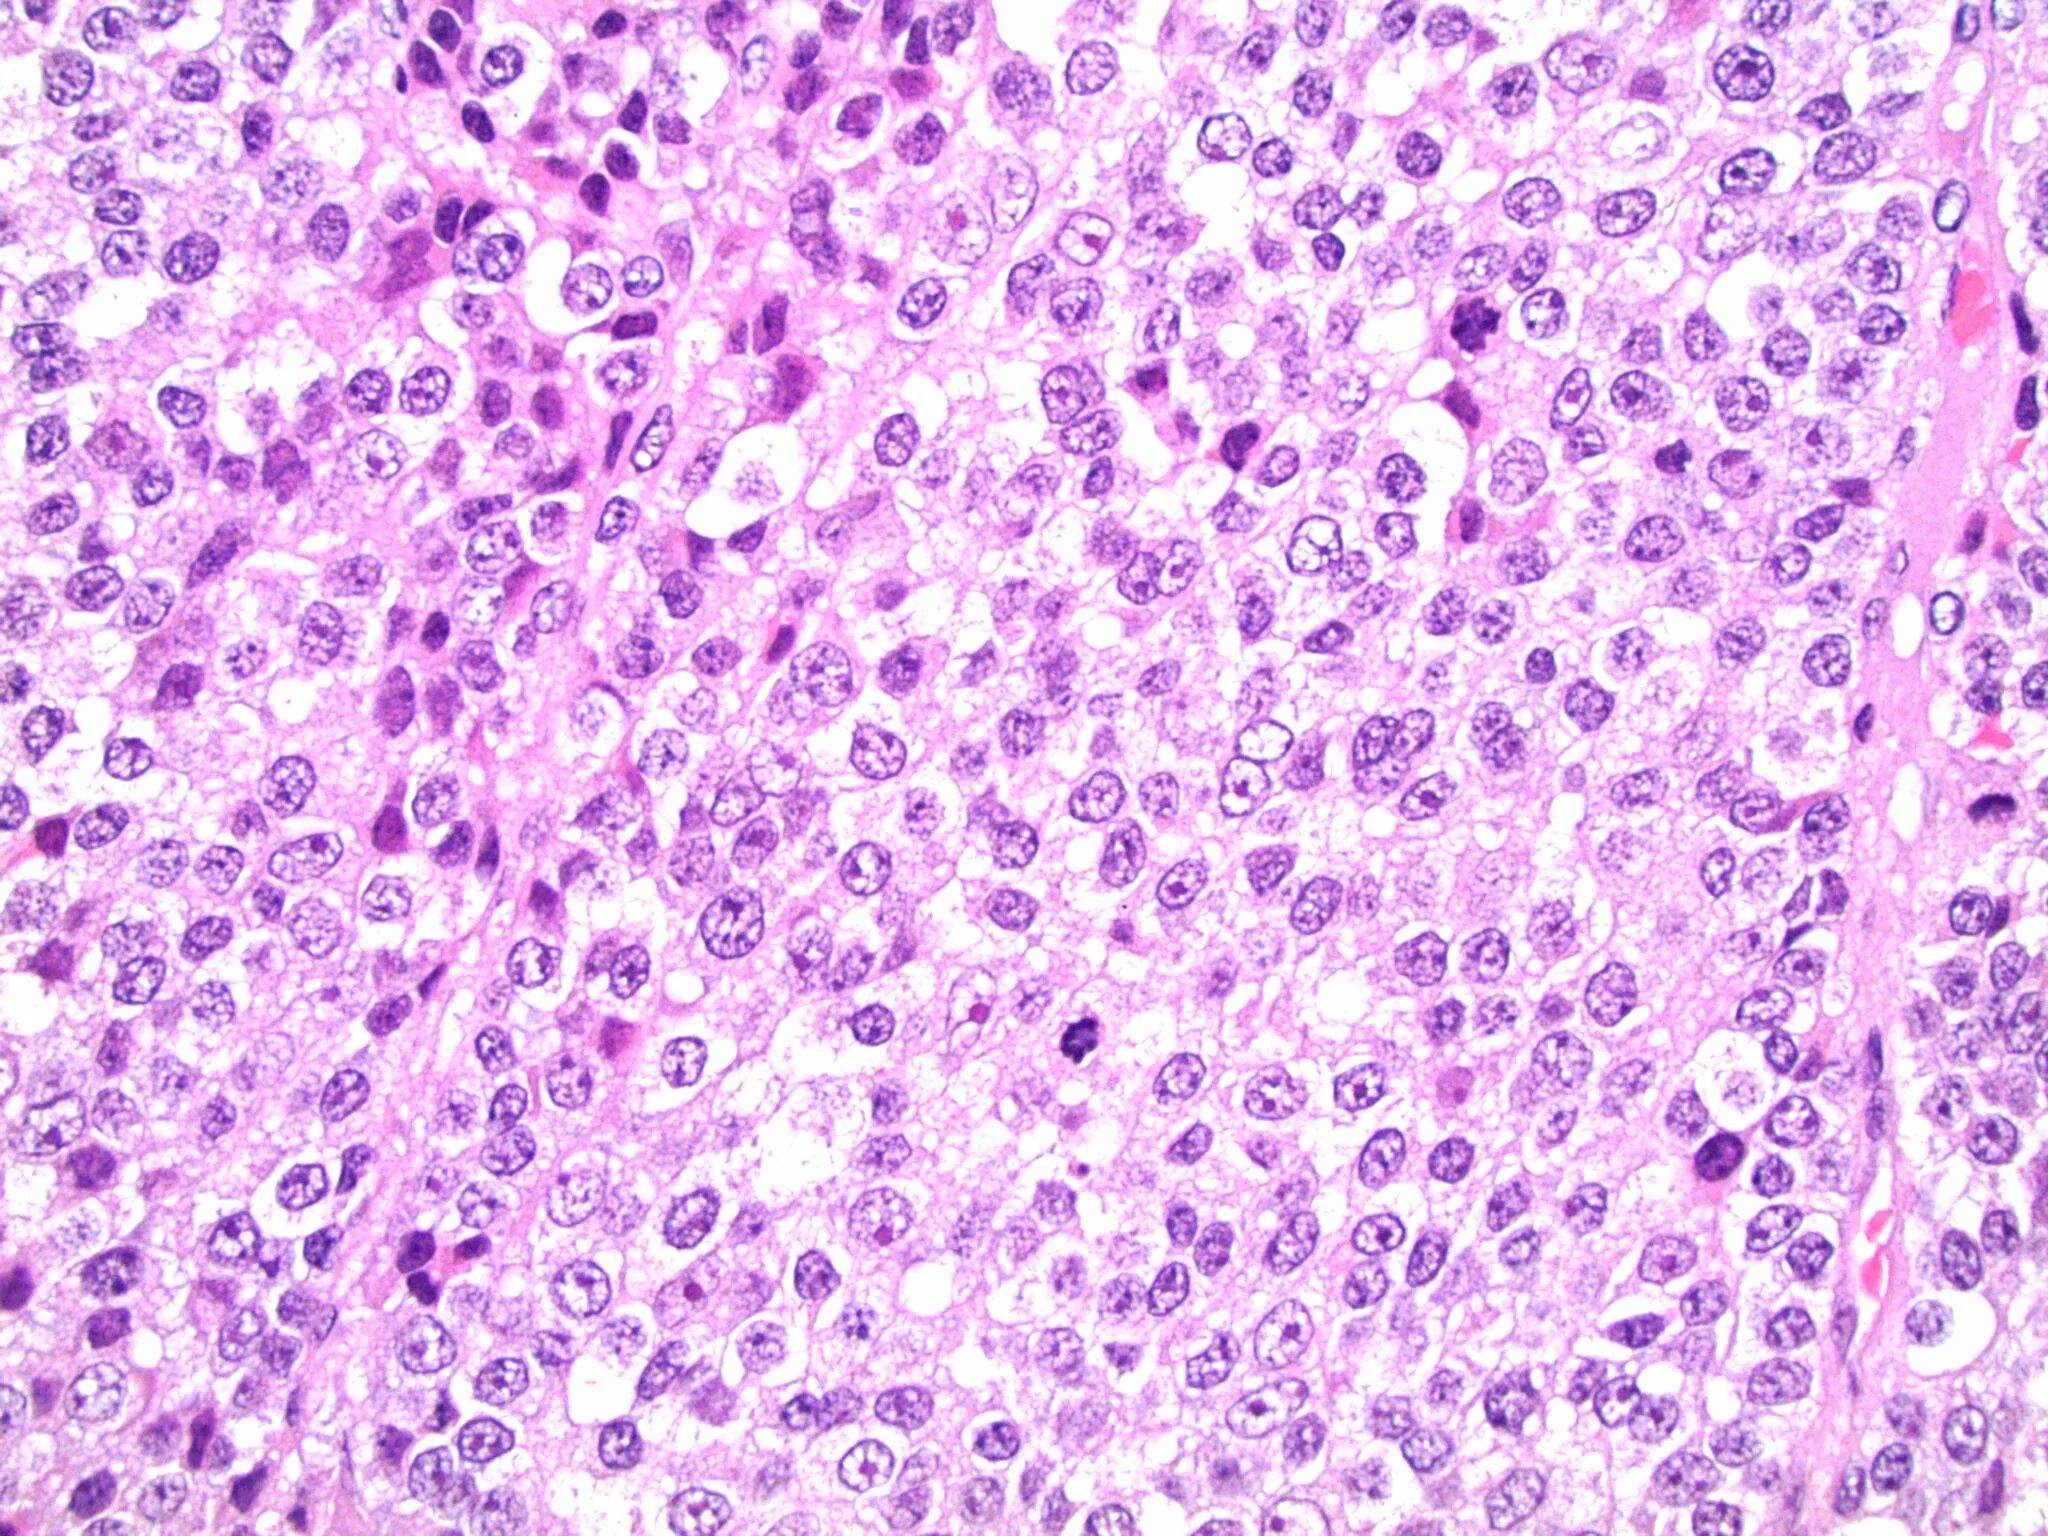

Патанат